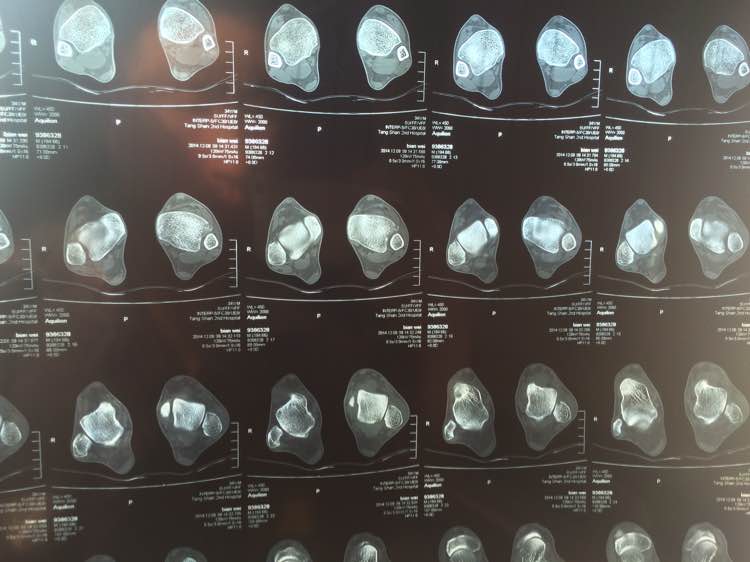

求高手刚我看看 骨折了吗

医院说骨折了 找的老中医说错位了 我晕了

左胫骨下段外侧端撕脱性骨折。